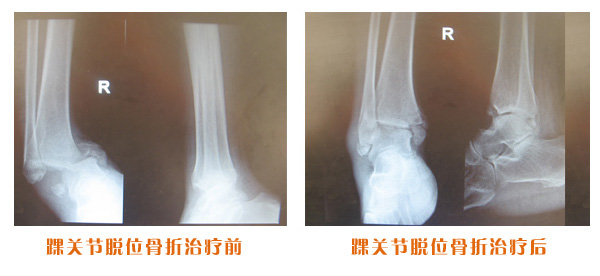

踝關節脫位骨折治療前后對比

尺橈骨骨折治療前后